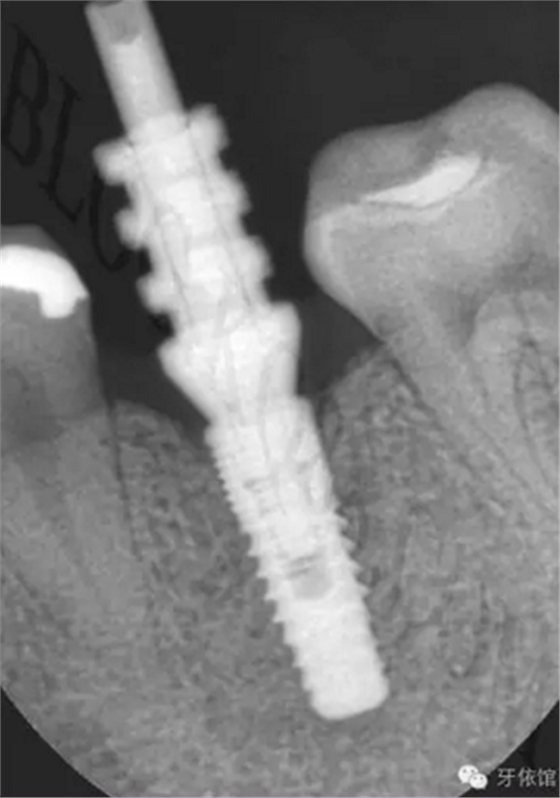

患者:女,28歲,此x光片為4年前拍的,左下6已于四年前行種植修復(fù),今天主要介紹右下6種植修復(fù)過程。計(jì)劃微創(chuàng)種植。

右下6口內(nèi)照片顯示牙槽嵴頂寬度并不是很充足,微創(chuàng)種植有一定的風(fēng)險(xiǎn),跟患者協(xié)商后,同意微創(chuàng)種植。

連接印模帽后拍x光片,檢查印模帽與種植體之間是否緊密相連。